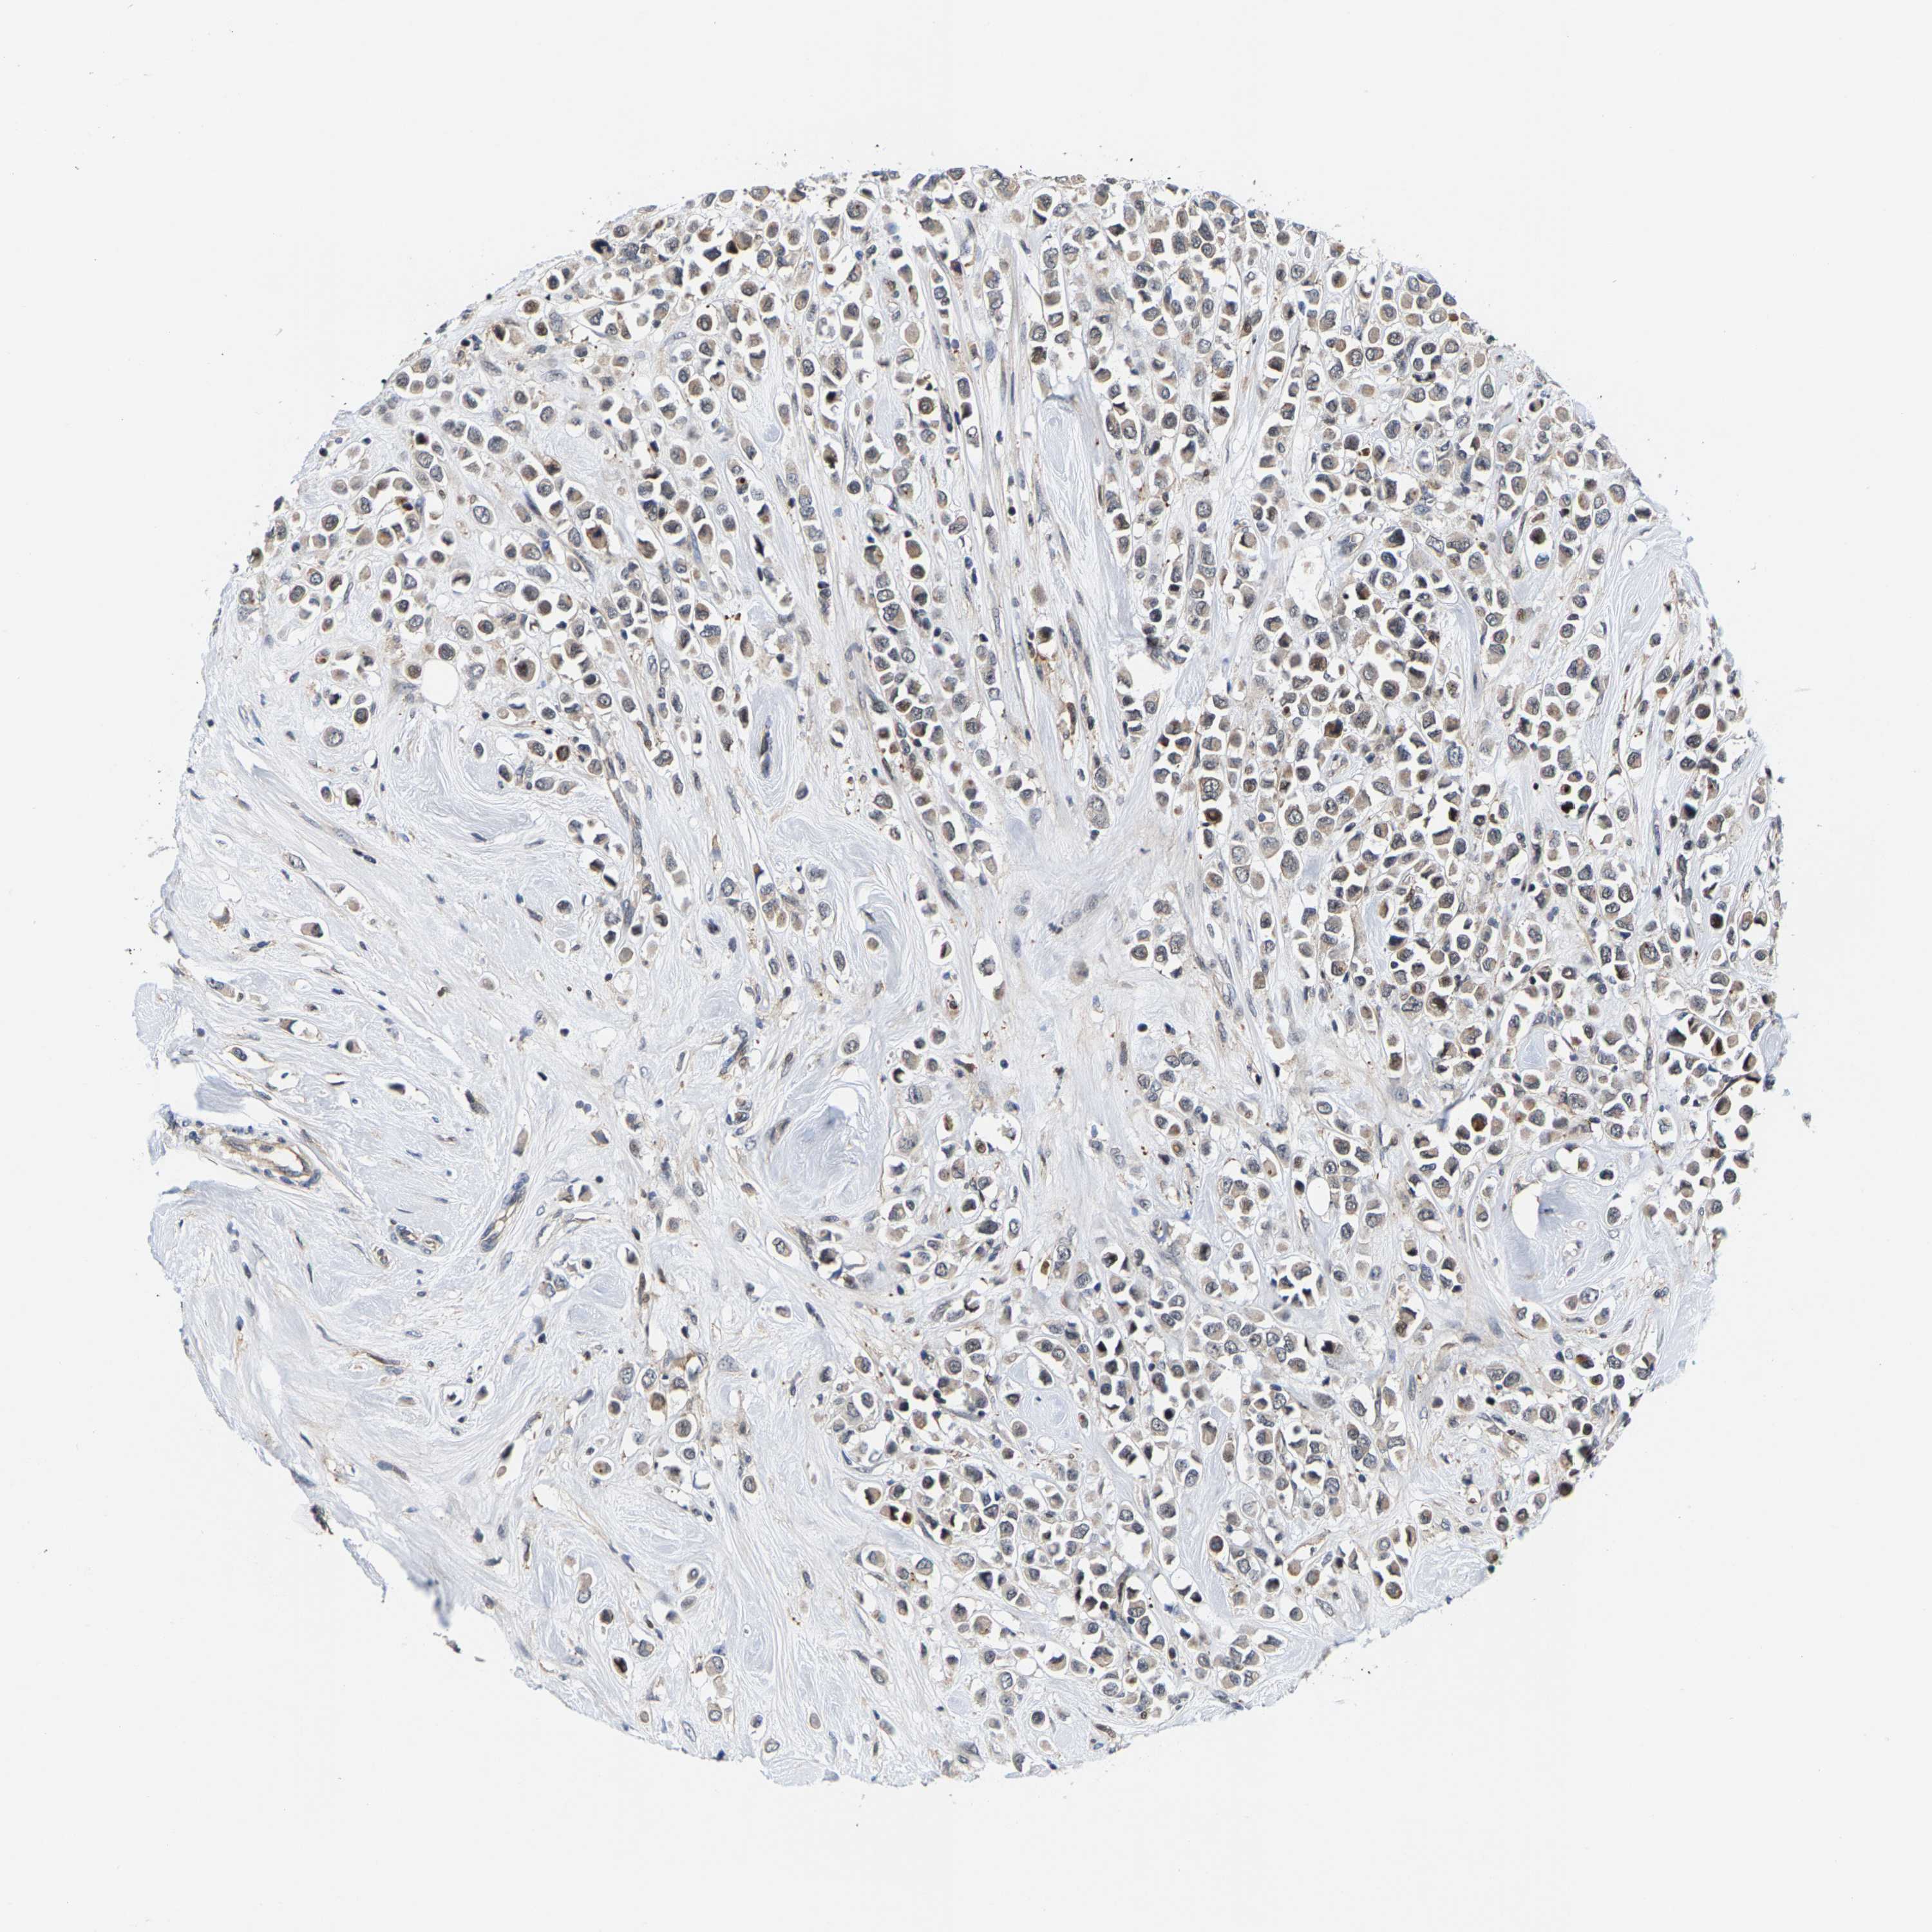

CANCER BREAST CANCER Show tissue menu

BRCA TCGA BRCA VALIDATION PROTEIN EXPRESSION